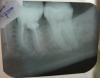

gea_rus Опубликовано 16 марта, 2011 Автор Поделиться Опубликовано 16 марта, 2011 (изменено) Продолжение историиЗуб посмотрели несколько врачей. В настоящий момент, при попытке полностью убрать пломбу, обнаружился перелом корня, без смещения. Врач настаивает, что он был уже до её вмешательства. Перелом заполнен прорутом. Прогноз, говорит, замечательный. Якобы, больно накусывать было из — за этого. Теперь все «зарастет». Боль от холодного, считает врач, скорее всего от 37 зуба. В следующее посещение планируется его депульпация. С 36 -м планируется гемисекция, с удалением дистального корня. Болевые и холодовые реакции не изменились. Прикладываю новый снимок. Почему — то стойкое ощущение, что что — то не так. Мне соглашаться на такой план лечения? Изменено 16 марта, 2011 пользователем gea_rus Ссылка на комментарий

juli63 Опубликовано 16 марта, 2011 Поделиться Опубликовано 16 марта, 2011 не хочется вас расстраивать,но, по моему, стало только хуже. Ссылка на комментарий

zybnaya feya Опубликовано 17 марта, 2011 Поделиться Опубликовано 17 марта, 2011 (изменено) не хочется вас расстраивать,но, по моему, стало только хуже.мдяяя "лучшее враг хорошего" в кривых руках Зарасти теперь может лунка,после удаления этого зуба.Какая там гемисекция?А потом что,повесят коронку целого моляра на 1 корень? Так и второй переломается. Очень жаль,но зубу конец. Переломы ПроРутом не закрывают ,а причиной болей кроме перелома,яаляются непролеченные нормально каналы. П.С не трогайте ради Бога 37,он то в чем виноват??? Меняйте врача Изменено 17 марта, 2011 пользователем zybnaya feya Ссылка на комментарий

gea_rus Опубликовано 17 марта, 2011 Автор Поделиться Опубликовано 17 марта, 2011 (изменено) Этот врач уже пятый. И это не шутка. Я поэтому и обратилась к Вам на форум с вопросом, есть ли дальше смысл лечить 36 зуб? Врачи обещают улучшение. Его не происходит. Насчет гемисекции, доктор так и сказала как описала зубная фея. На половину зуба смастерить коронку. "Хоть половина, но зато свой зуб. Удалить всегда успеем.". Уважаемые врачи форума, что может давать реакцию на холодное в районе 35,36 зуба если 34, 35,36 депульпированы? Есть ли необходимость депульпировать 37? Ночью не болит ни кто. накусывать на него толком не получается из -за 36. Я в отчаянии. Изменено 17 марта, 2011 пользователем gea_rus Ссылка на комментарий

zybnaya feya Опубликовано 17 марта, 2011 Поделиться Опубликовано 17 марта, 2011 Уважаемые врачи форума, что может давать реакцию на холодное в районе 35,36 зуба если 34, 35,36 депульпированы? Есть ли необходимость депульпировать 37? Ночью не болит ни кто. накусывать на него толком не получается из -за 36. Я в отчаянии. Удаление 36 с последующей имплантацией-протезированием Перелечить каналы в 34,35- они по 3-4 мм недопломбированны. Возможен "остаточный пульпит" . Покрыть их коронками. Если есть кариес на 37 -запломбировать. Не депульпировать. Ссылка на комментарий